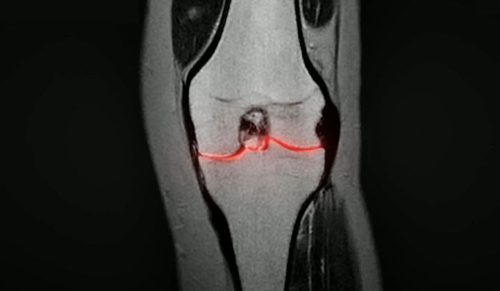

퇴행성 관절염은 몸속 조직이 퇴화가 되고 퇴행성 변화가 생기면서 연골이 손상되고 닳아서 생기는 것입니다. 즉, 관절과 관절 사이에 연골이 있어야 하는데 연골이 얇아지고 손상되고 닳아버리면서 관절 뼈 끼리 부딪히게 되고, 이로인해 염증이 생겨 통증반응이 심하게 아픔을 주게됩니다. 그리고 무릎이 뻣뻣하거나 압박당하는 듯한 통증 또한 퇴행성 관절염의 대표 증상인데, 이때 구절초 추출물을 섭취하게 되면 리나린 성분이 관절염을 유발하는 염증을 억제하는데 도움을 줍니다.

③ 연골 손상 감소 - 드르륵 무릎 소리 완화

무릎에서 나는 뚜두둑 소리는 문제 없는 일반 관절에서도 날 수 있는 소리지만, 드르륵하는 무언가 갈리는 것 같은 소리는 연골 손상을 의심해봐야 합니다. 연골이 정상인 경우 관절이 움직여도 손상이 없지만, 연골이 닳아서 드러난 뼈와 건강한 연골이 맞닿는다면 건강한 연골마저 손상되어 관절염을 유발합니다. 또한, 관절염이 생긴 뼈끼리 맞닿으면 드르륵 소리가 발생하고 통증이 생기게 됩니다. 연골은 재생이 안되기 때문에 연골이 닳기 전에 관리하는 것이 중요하며, 관절 통증 개선을 위해 운동을 포함한 여러 가지 노력이 필요합니다. 구절초 추출물 속 리나린 성분이 연골세포에 영향을 주어 연골 손상을 줄여줄 수 있습니다.